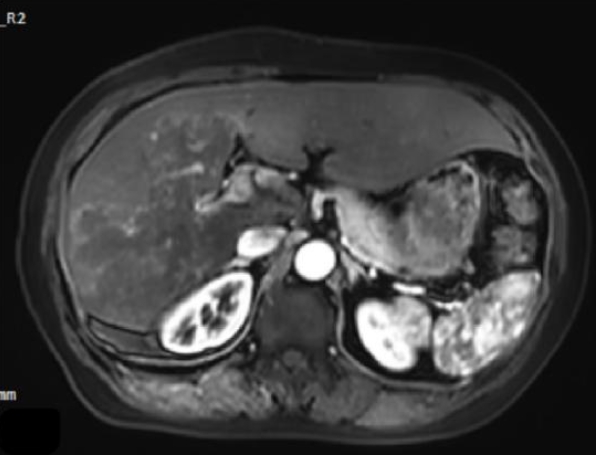

Magnetic resonance imaging showed irregular, slightly hyperintense T1 signals in the right lobe and caudate lobe (14.5×9.6×11.5 cm) without enhancement. The capsule showed enhancement, with inferior vena cava locally compressed. Diffusion-weighted imaging revealed slightly high signals (Fig. 3). T2-weighted imaging showed irregular, slightly hyperintense T2 signals in the right lobe and caudate lobe, with high diffusion-weighted imaging signals. A round, hyperintense T2 lesion (1.6×1.3 cm) was seen in the left adrenal gland (Fig. 4A, B). The absence of typical multilocular cystic structures cannot rule out HAE, as the disease may present as a solid, pseudotumoral mass with central necrosis and peripheral fibrosis, especially in endemic areas.

Fig. 4.

(A) Magnetic resonance imaging T2-weighted imaging demonstrates mildly prolonged T2 signal in the right hepatic lobe and caudate lobe. (B) A round-shaped, hyperintense T2 signal lesion is observed in the left adrenal gland, which also shows high signal intensity on diffusion-weighted imaging.

Fig. 4. (A) Magnetic resonance imaging T2-weighted imaging demonstrates mildly prolonged T2 signal in the right hepatic lobe and caudate lobe. (B) A round-shaped, hyperintense T2 signal lesion is observed in the left adrenal gland, which also shows high signal intensity on diffusion-weighted imaging.